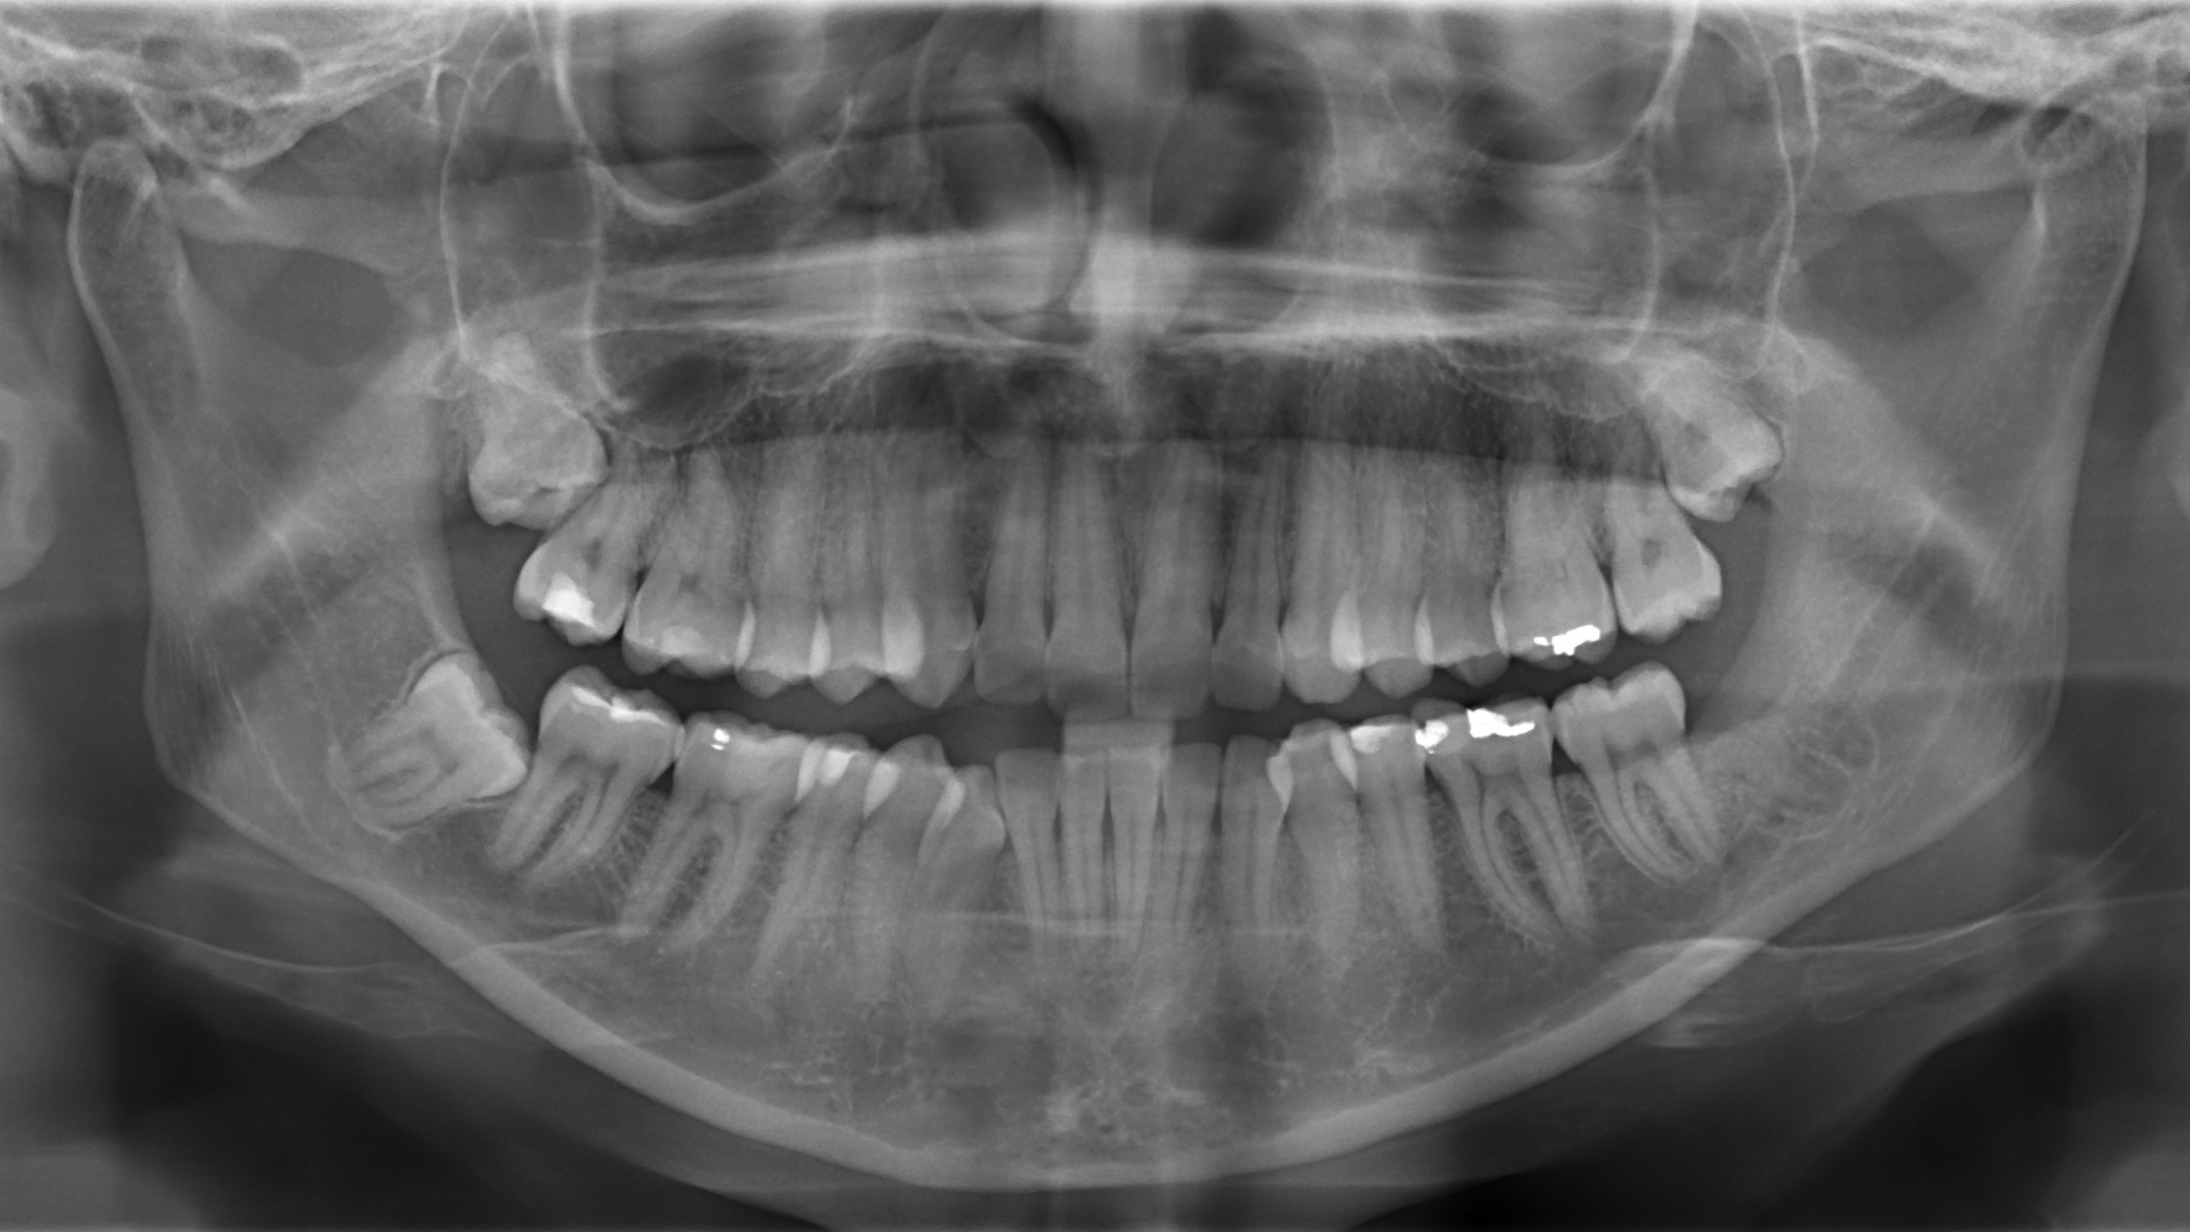

L’utilizzo della radiologia digitale anche nelle classiche forme Endorale e Oropanoramiche  permette una qualità migliore e una ridotta esposizione per il paziente.

Ortopanoramiche digitali

In odontoiatria, per effettuare una corretta diagnosi e un corretto piano di trattamento, è fondamentale eseguire approfonditi esami radiologici.

In particolare, nella moderna terapia implantoprotesica l’esame radiologico è importante perché è l’unica indagine che permette di studiare bene le ossa mascellari del paziente per inserire in maniera corretta gli impianti dentari.